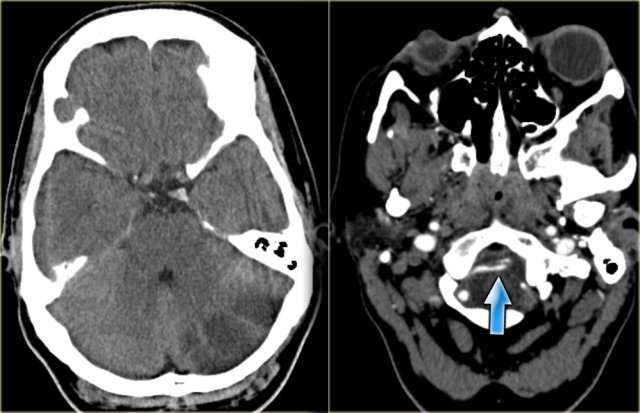

On the left CT-images of a left-sided PICA-infarction.

Notice the posterior extention.

The infarction was the result of a dissection (blue arrow).